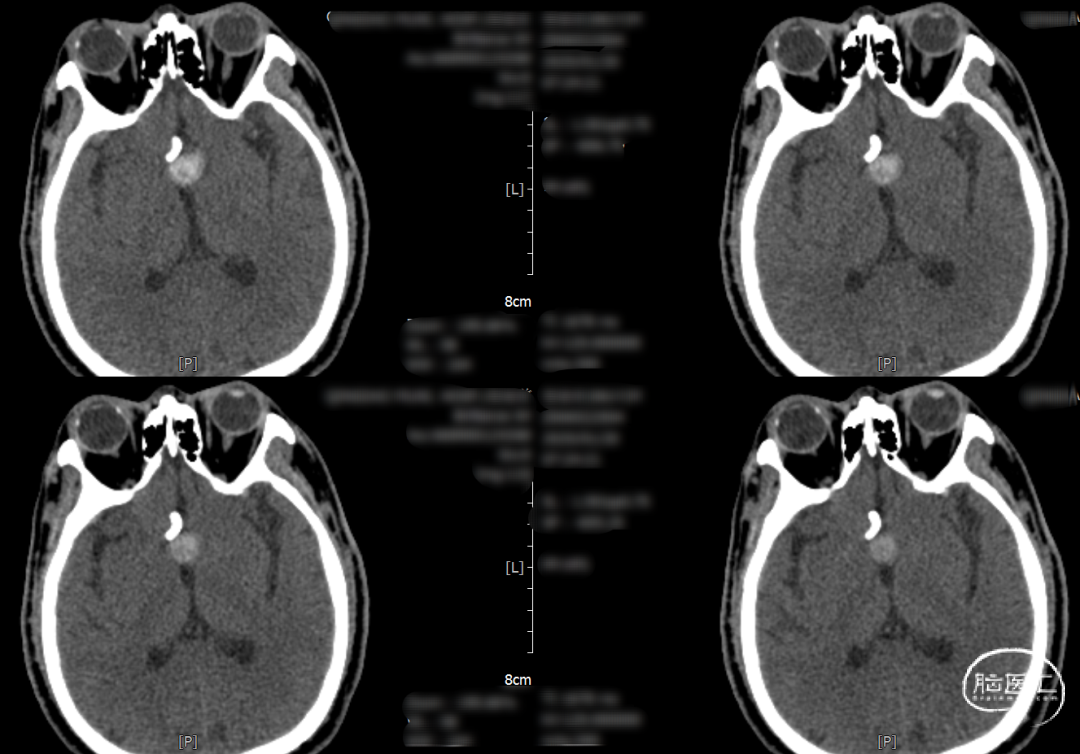

辅助检查示:2025-01-08 鞍区及垂体MR平扫:鞍内及鞍上肿瘤,垂体瘤并卒中?建议鞍区及垂体MR增强扫描。

2025-1-19 DSA造影3D重建及方案讨论:

DSA造影3D重建测量

术后一天检查。